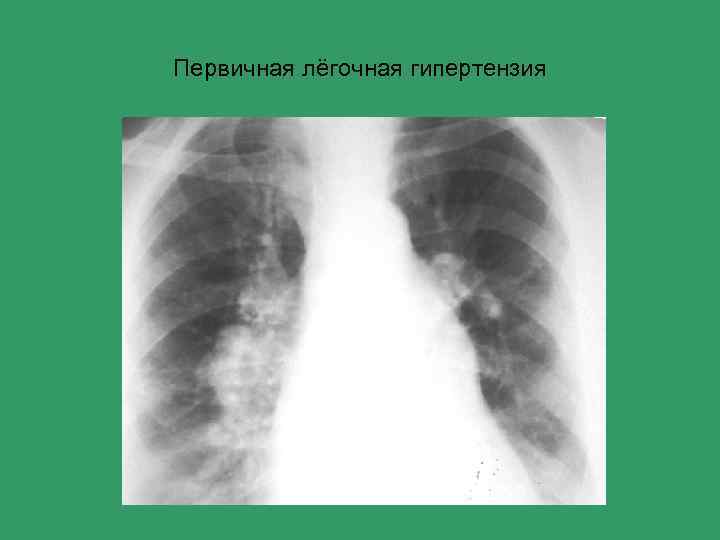

Первичная лёгочная гипертензия